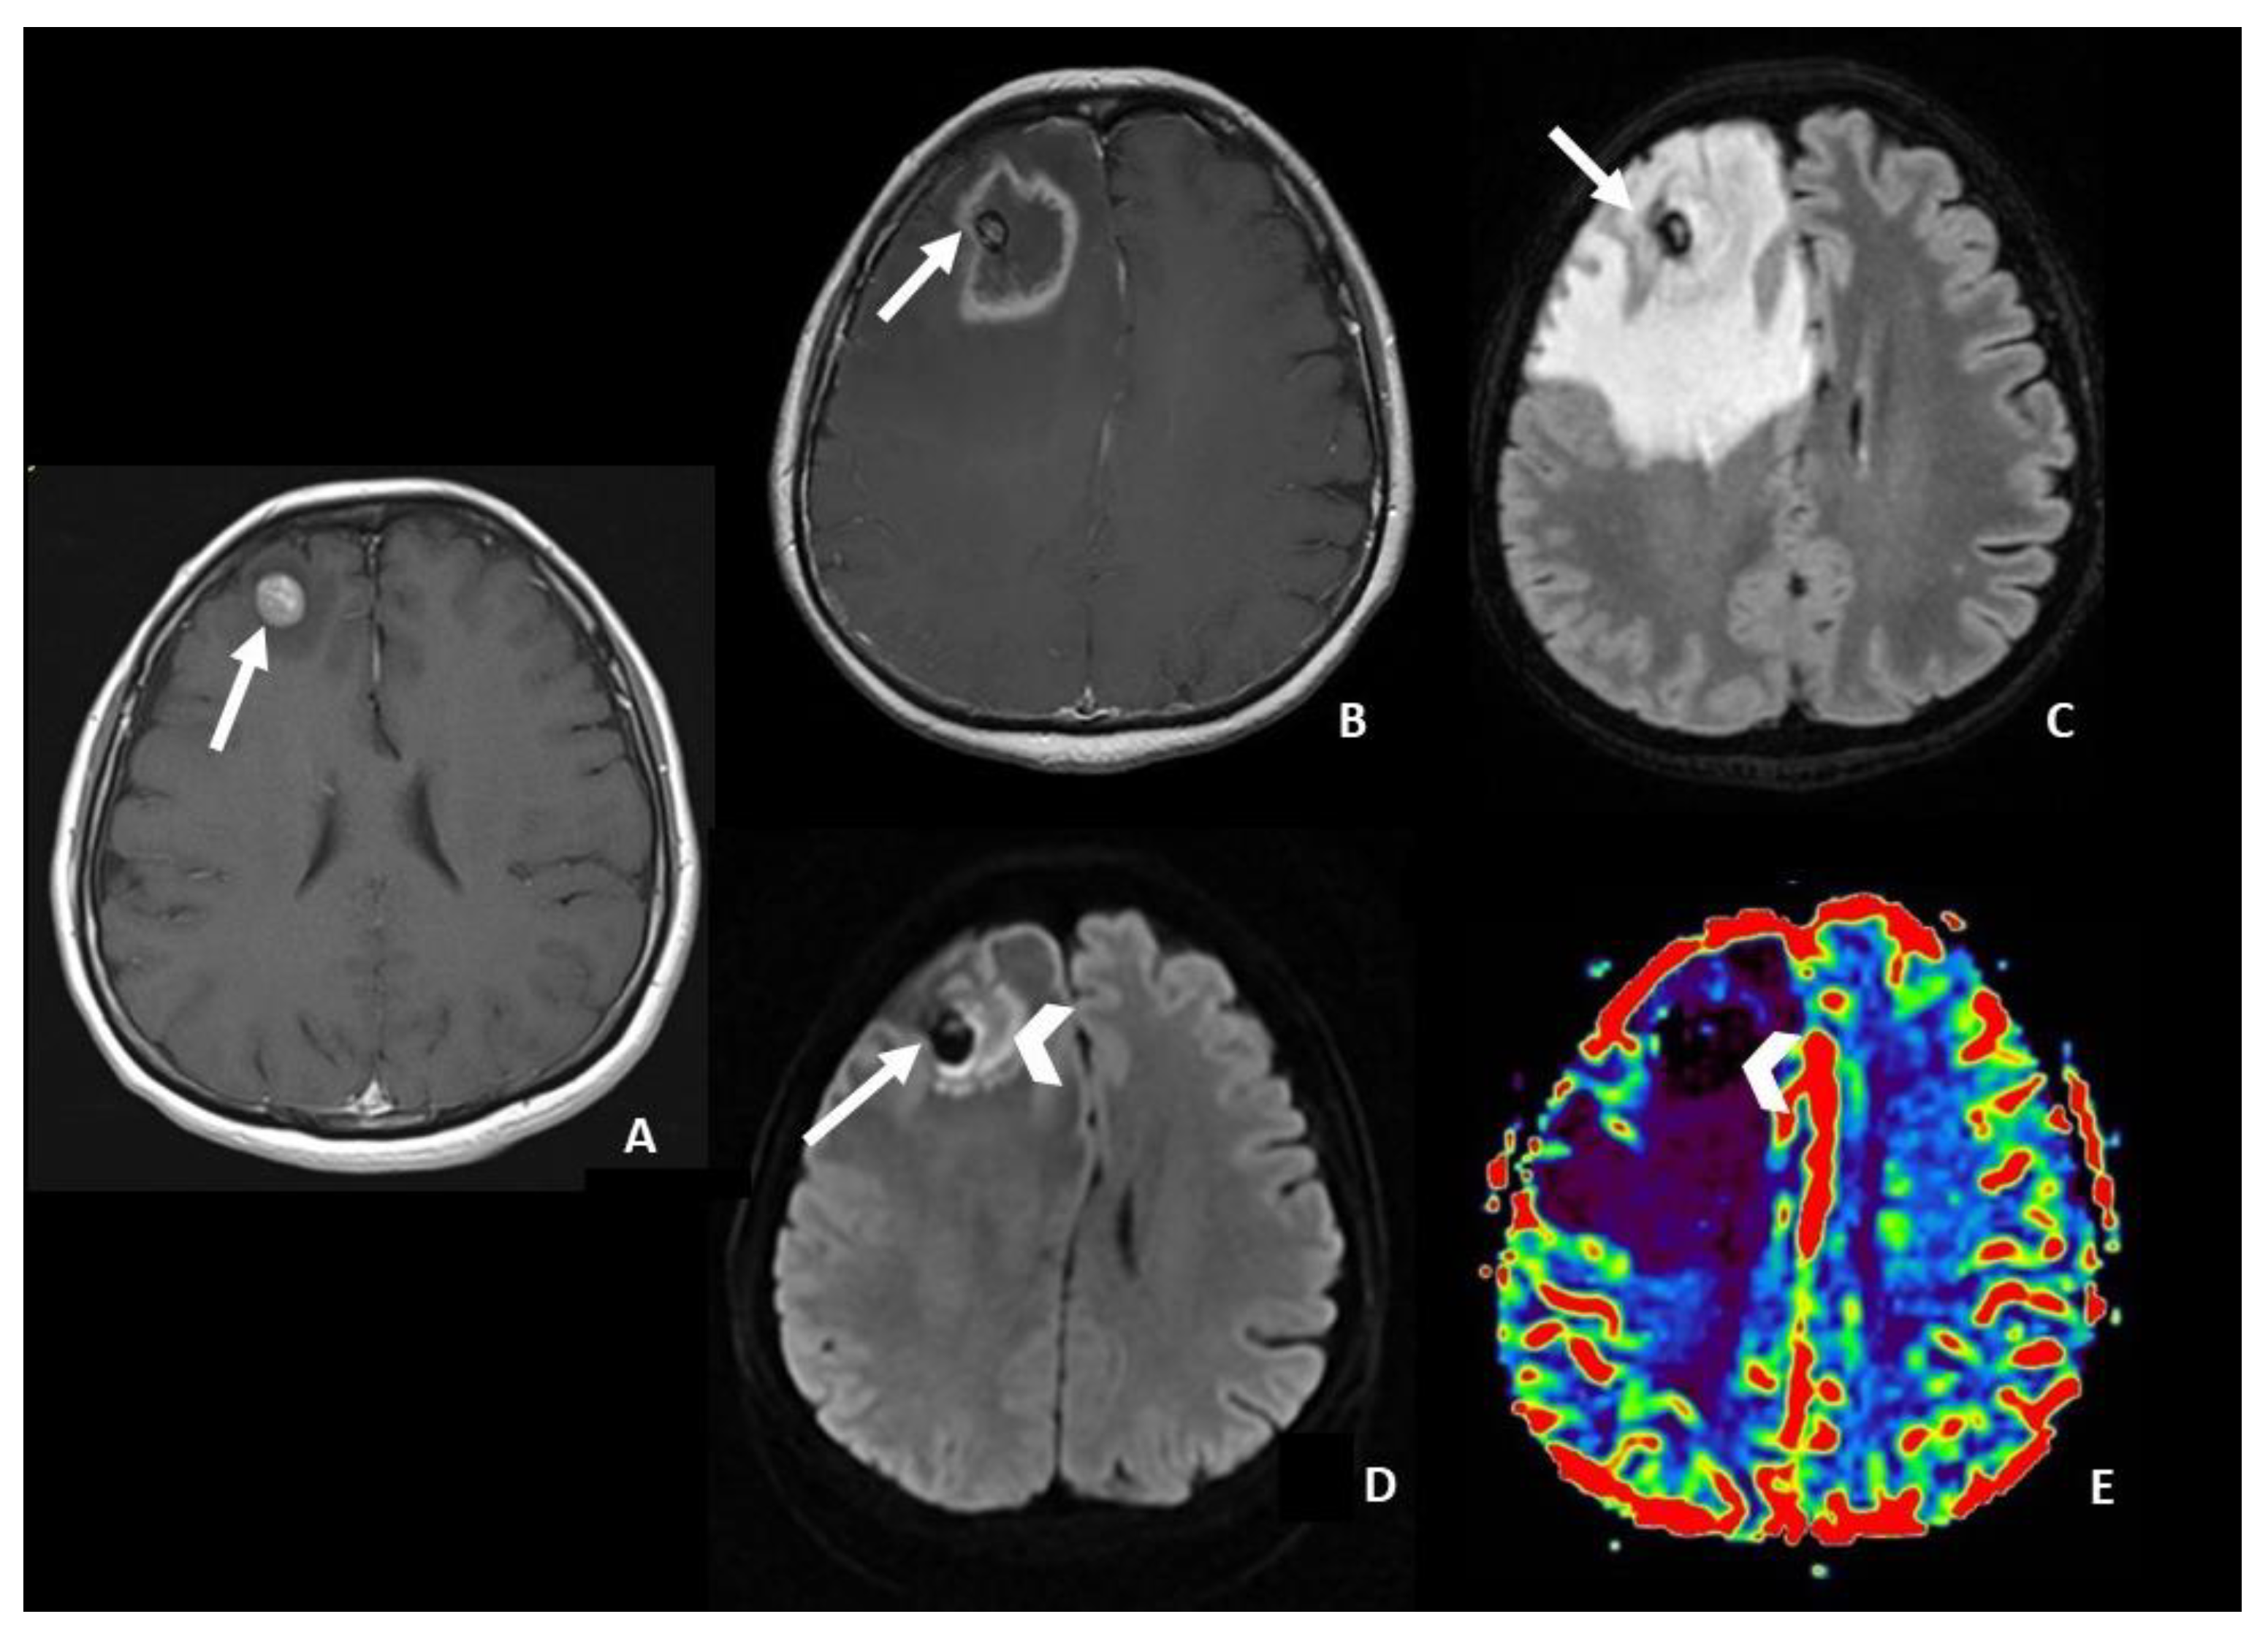

- In DWI/ADC images, “The centrally restricted diffusion sign” appeared to be due to hypercellularity in coagulative necrosis and theexpression of RN.

- central restricted diffusivity (“the centrally restricted diffusion sign”) (Figure 1)

- Hainc, N.; Alsafwani, N.; Gao, A.; O’Halloran, P.J.; Kongkham, P.; Zadeh, G.; Gutierrez, E.; Shultz, D.; Krings, T.; Alcaide-Leon, P. The Centrally Restricted Diffusion Sign on MRI for Assessment of Radiation Necrosis in Metastases Treated with Stereotactic Radiosurgery. J. Neurooncol. 2021, 155, 325–333. [Google Scholar] [CrossRef]